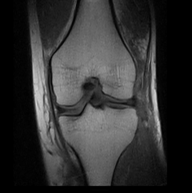

5.3 Out-of-Domain Generalisation

One way to test the generalization capability of the trained X-Diffusion is to test it on a completely different domain from an MRI dataset not seen during training. We report the single-slice results on NYU fastMRI [37, 82], a knee MRI dataset, using the X-Diffusion trained on the BRATS brain MRIs. The results are shown in Figure 9 and Table 2. It shows how successfully X-Diffusion is able to generate knee MRIs from a single image, despite not seeing knees at all in training. To qualitatively assess how realistic our generated 3D volumes were (produced from a single slice), we gave 20 generated examples alongside their real MRI counterparts to an expert orthopaedic surgeon. He was then asked to identify the real example from a given pair. The surgeon identified with certainty only 10 real knee MRIs out of 17, while could not decide on the remaining 3 of the 20 MRI pairs. This further validates the generated out-of-domain MRIs.